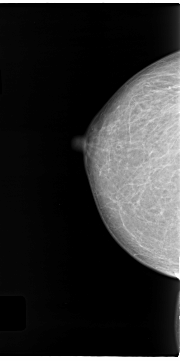

C_0122_1.RIGHT_MLO

RIGHT_MLO LINES 4696 PIXELS_PER_LINE 2568 BITS_PER_PIXEL 12 RESOLUTION 50 NON_OVERLAY